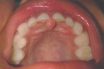

Incisive papilla

The elevation of soft tissue covering the foramen of the incisive or nasopalatine canal. A small bump in the mucosa above and just to the front of the incisive foramen at the very front of the hard palate. The papilla is used as an injection site when anesthetizing the nasopalatine nerve.

Incisive foramen

An anatomic hole, usually found lingual to the maxillary central incisors, that allows passage of the vascular and neural tissues that supply the anterior maxilla. Foramen of the incisive canal containing the nasopalatal nerve and accompanying blood vessels. It is located just palatal to the two maxillary central incisors along the median suture. Small opening…